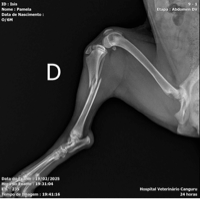

Eu sou a Pamela,preciso de 2,500 reais para a cirurgia ortopedica da minha cachorrinha filhote,que foi atropelada por um carro em alta velocidade!Quebrou a tibia e fibula,e teve descolamento de varias pedaços de pele pelo corpo!Qualquer valor é bem vindo!Nao tenho condiçoes financeiras de arcar com tudo!Por favor aceito qualquer valor,sendo de coracao e sincero!Só vim pedir essa ajuda pois,nao tenho como arcar com tudo!A pessoa atropelou e saiu correndo sem prestar nenhum socorro!Desde ja agradeço a atençao e carinho♥️🙏